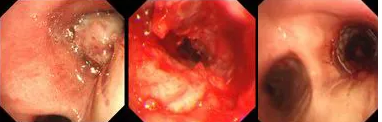

原來,秦爺爺入院時診斷為“右主支氣管”鱗狀細胞癌伴壞死。他的右主支氣管被腫瘤完全堵塞,混合性狹窄。面罩吸氧10升/分的狀況下,指脈氧只有85%,無法平躺,呼吸困難,病情十分危急,隨時有生命危險。

經(jīng)評估并與家屬溝通同意后,歐陽海峰副院長決定為患者實施TTS氣道支架手術。手術當天,在麻醉手術中心的配合下,歐陽海峰副院長為患者在局麻下快速凍切腫瘤組織,實現(xiàn)右主支氣管再通,并經(jīng)氣管鏡活檢孔道迅速植入14*30 TTS支架一枚。支架植入過程耗時僅6秒,迅速緩解了患者的氣短瀕死癥狀。